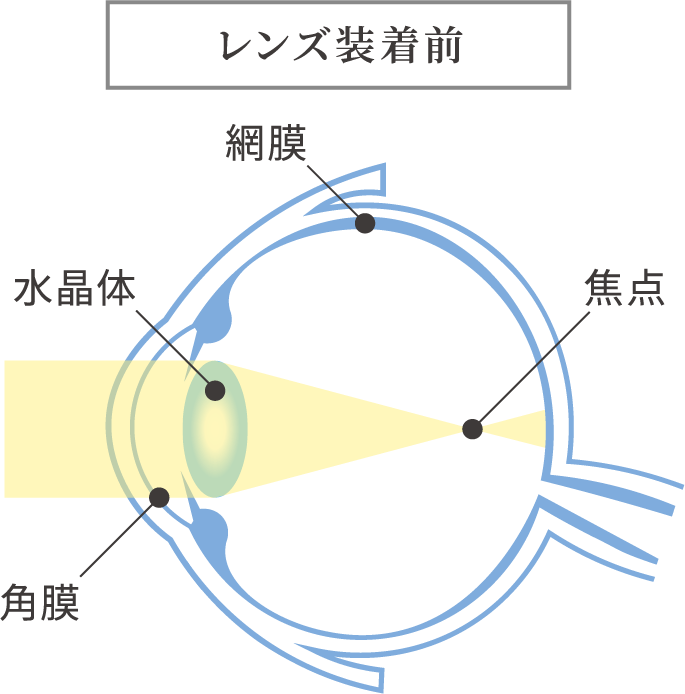

近視は幼児期、学童期、思春期を通し、主に眼の長さが伸びることで、焦点の合う距離が近くなり、焦点距離が近くなればなるほど遠くの像がぼやけてしまいますので、視力が低下します。

近視にはもともと備わっているピント調節機能が関わっています。

眼は近くを見るときには調節力を使ってピントを合わせています。

目にする対象物が近い距離にあればあるほど、この調節力を強く使わなければなりません。

これが問題となり以下の機序が働き、近視は発症し、進行すると考えられています。

- 遠視性デフォーカスと調節ラグ

- 軸外収差

- 目の中に入ってきた像を網膜が感じ取りますが、

網膜の中心から少し離れた場所におこるぼやけのこと